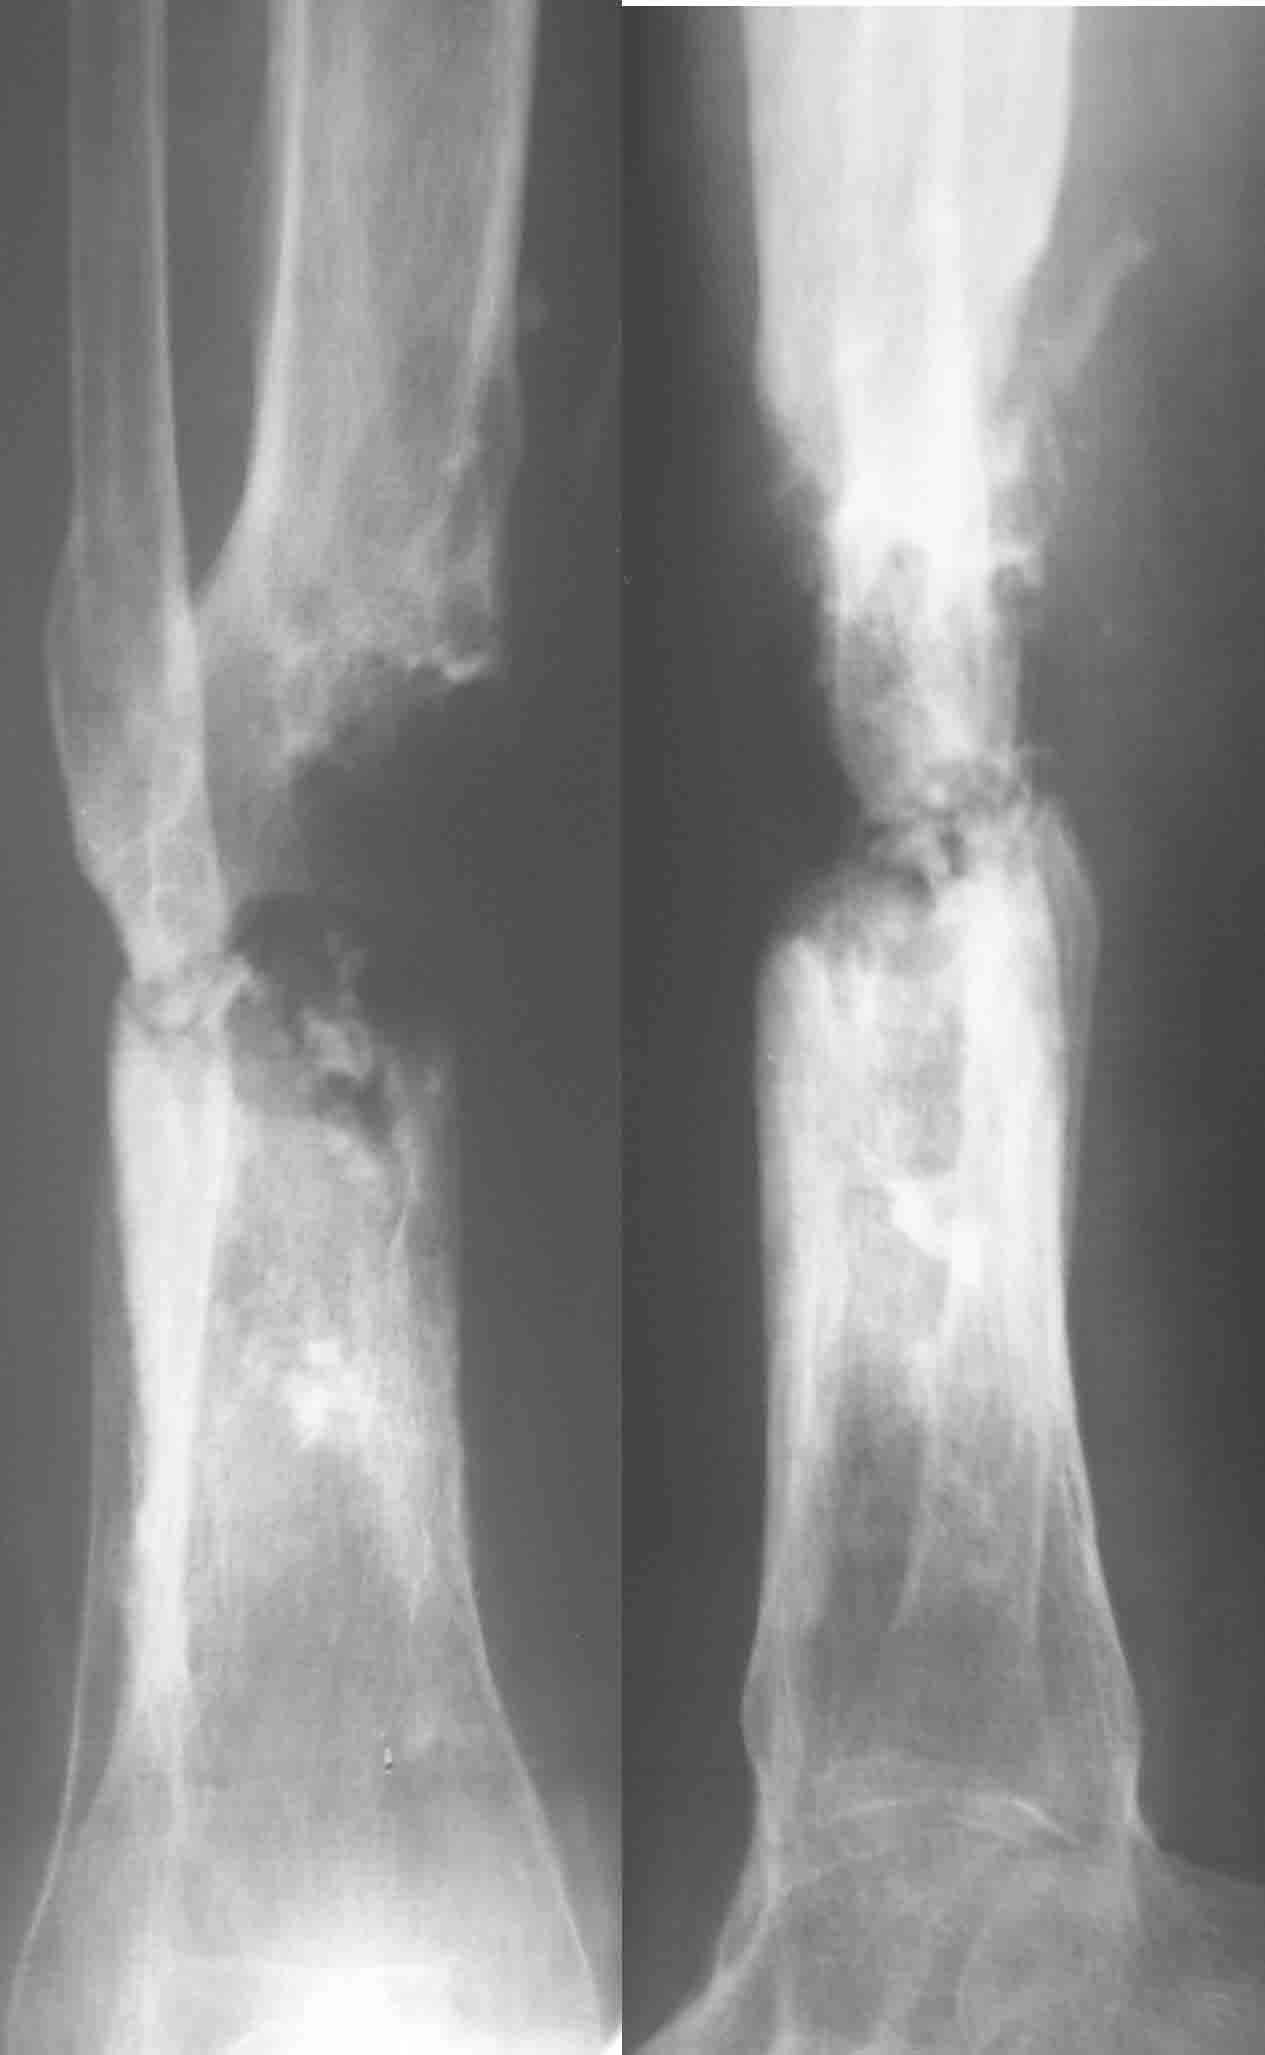

Итак, в настоящий момент больной пришел к нам с полной нагрузкой на оперированную конечность и с такой картиной (см. приложение). Участок мягких тканей с передней стенкой нижней трети ББК, выгнил и представляет дефект 2×2,5 см. На перевязке - циркулярный(?) некроз костной трубки.

Выкладываю картинки похожей пациентки. Извините, что без окончательных снимков (сейчас их нет под рукой). Правда мы имели проблемы у данной больной после снятия аппарата, когда промежуточный фрагмент большеберцовой кости сместился на 1,5 см дистально и отошел от проксимальной части кости. До сих пор у пациентки на снимках определяется лишь тонкая полоска кости по задней поверхности за штифтом (образовалось что-то вроде маленького регенерата)в области стыковки промежуточного и проксимального фрагментов. Больная пока решила подождать. Не хочет оперироваться, так как ходит не хромая, работает.

Добавляю свой пятак, не дожидаясь завершения случая, который приберегал "на третье". Выбрал фото мягких тканей.

Кратко: мужчина за 60 лет получил травму 28 лет назад (переехало автобусом). Оперировался десятки раз, в итоге с очередным патологическим переломом, хронической язвой и гипсовой лонгетой попал ко мне... Объективно - остеомиелит, инфицированный ложный сустав (или как его назвать), флегмона по наружной поверхности

голени, укорочение около 5 см.

На операции резекция 8 см, внешний остеосинтез,одновременное сближение примерно на 4 см, а затем постепенное сближение до полного контакта в течение 3 недель. Рана с патологически измененными краями, имевшая на операции размеры примерно 4-5 на 10-12 см закрылась самостоятельно в течение примерно 2-х мес. Ну не самостоятельно, конечно, а с нашей помощью, но без пластики.

Сейчас в аппарате вытянул около 6 см в верхней трети.